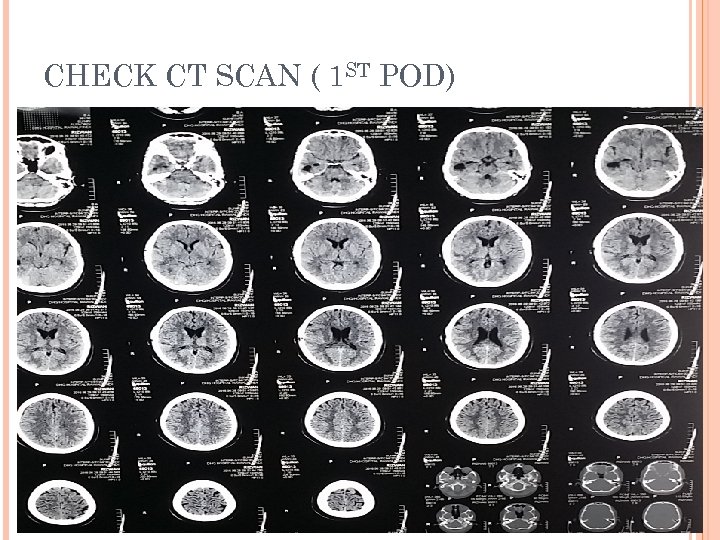

CHECK CT SCAN ( 1 ST POD)

POSTOPERATIVE PERIOD Patient conscious oriented Taking orally Pus for C/S showed proteus mirabilis. Discharged on 4 th POD with iv antibiotics ( 4 weeks ). Advised: Wound care Daily dressing OPD follow up after 10 days.